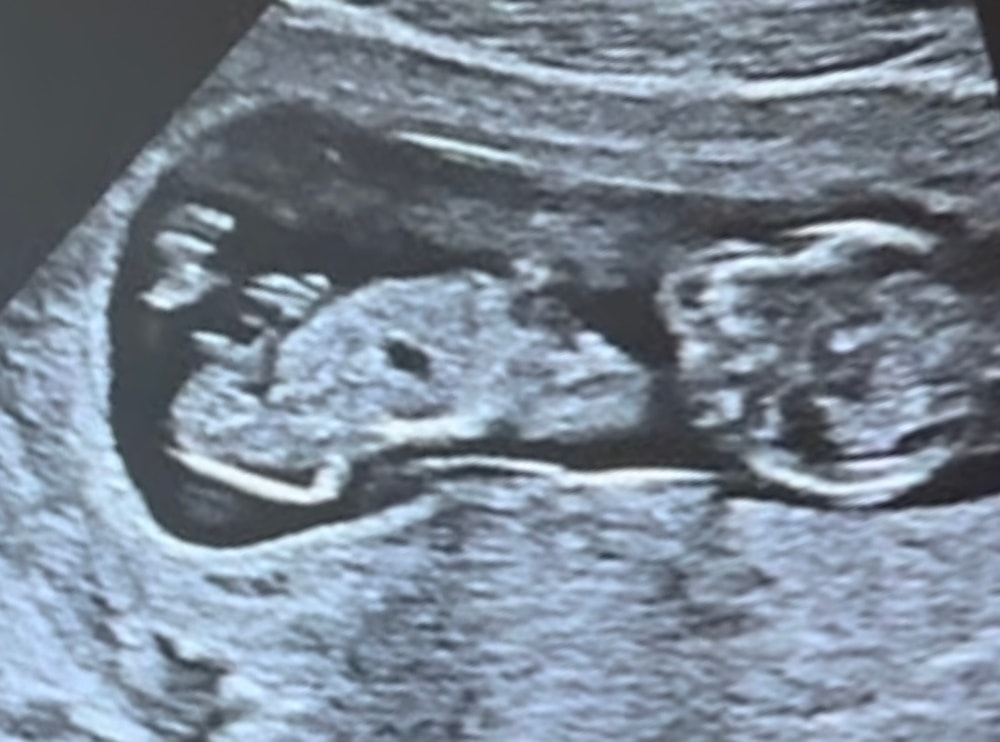

Пол по узи, 1 скрининг

Пол малышаВсем привет. Сходила на первый скрининг. Знаю, что еще рано видеть пол, и что видят только опытные врачи. Но я не удержалась и спросила «не видно ли еще?». Врач сказала «я бы не так не сказала. Я могу сказать, что мальчик не определяется» - показала мне вид снизу. Ну в общем девочка по ее мнению. Но! Я на протяжении узи что-то сняла на видео, а дома до скрининга начиталась и насмотрелась тут на форуме на разницу половых бугорков. В итоге начала разглядывать эти видео, и такое ощущение, что мальчик все-таки определяется)))) Понимаю, что я не врач, но как будто это писюн! Как думаете?

Скрининг был на сроке 12.1 по месячным, по узи поставили 13.1.

Анастасия, так у Вас внизу, а у автора вверх торчит, прям как у моего сына с первого скрининга!

А мне кажется, это ножка на фото, а не половой бугорок. Никакого «писюна» на таком сроке еще нет.

В первый раз слышу что с писюном бывают девочки😳. У малыша писюн торчит, конечно это мальчик.

вот фото)